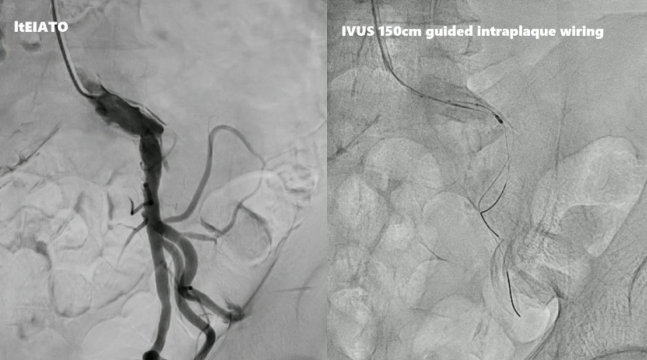

病例二:左侧髂外动脉完全闭塞

术者采用IVUS引导下精准导丝通过。目前,支架已有适用于经桡动脉介入的长鞘版本,因此可经桡动脉置入覆膜支架,通过造影和IVUS进行评估,可见支架植入后即刻效果理想。